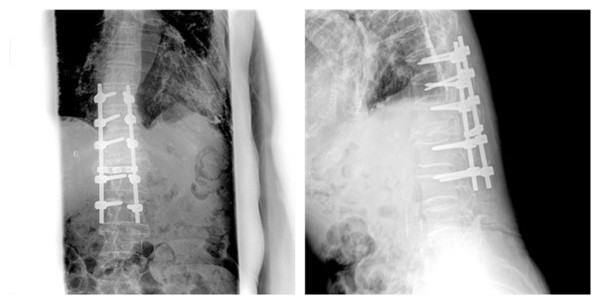

入住骨二科(脊柱外科)后,我们立即组织多学科会诊评估患者手术风险,特别是麻醉科多次前来评估患者,耐心指导患者术前注意事项。经过详尽而全面的术前准备,由李浩鹏教授亲自主刀,并邀请具有丰富经验的薛荣亮教授保驾护航,为患者顺利实施腰1截骨减压内固定术,解除脊髓压迫,患者术后三天即在支具保护下下床,观察伤口几日后顺利出院。

术后腰椎正侧位片